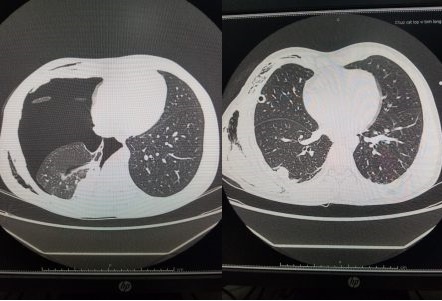

| Hình ảnh CT ngực trước và sau khi mổ. Ảnh: BVCC. |

Sau mổ 10 ngày, người bệnh được dẫn lưu hút áp lực liên tục không ra khí, chụp lại cắt lớp vi tính lồng ngực thấy phổi nở tốt, không thấy dịch khí khoang màng phổi 2 bên. Người bệnh đã được rút dẫn lưu và ra viện sau đó 2 ngày.

Tuy nhiên, sau khi xuất viện, người bệnh đột ngột thấy khó thở trở lại, không đau ngực và được chuyển vào Bệnh viện Đa khoa Tỉnh Quảng Ninh, phát hiện tràn khí khoang màng phổi phải mức độ nhiều, xẹp phổi phải thụ động, tràn khí dưới da.

Ca mổ đã được tiến hành kịp thời với phương pháp nội soi lồng ngực xử trí tổn thương. Trong mổ, các bác sĩ phát hiện tổn thương vỡ kén khí thủy trên phổi phải, tiến hành gỡ dính, cắt thùy trên phổi phải không điển hình, gây dính màng phổi chủ động bằng betadine đậm đặc và đặt 2 dẫn lưu khoang màng phổi. Sau mổ, người bệnh ổn định, chuyển hậu phẫu.